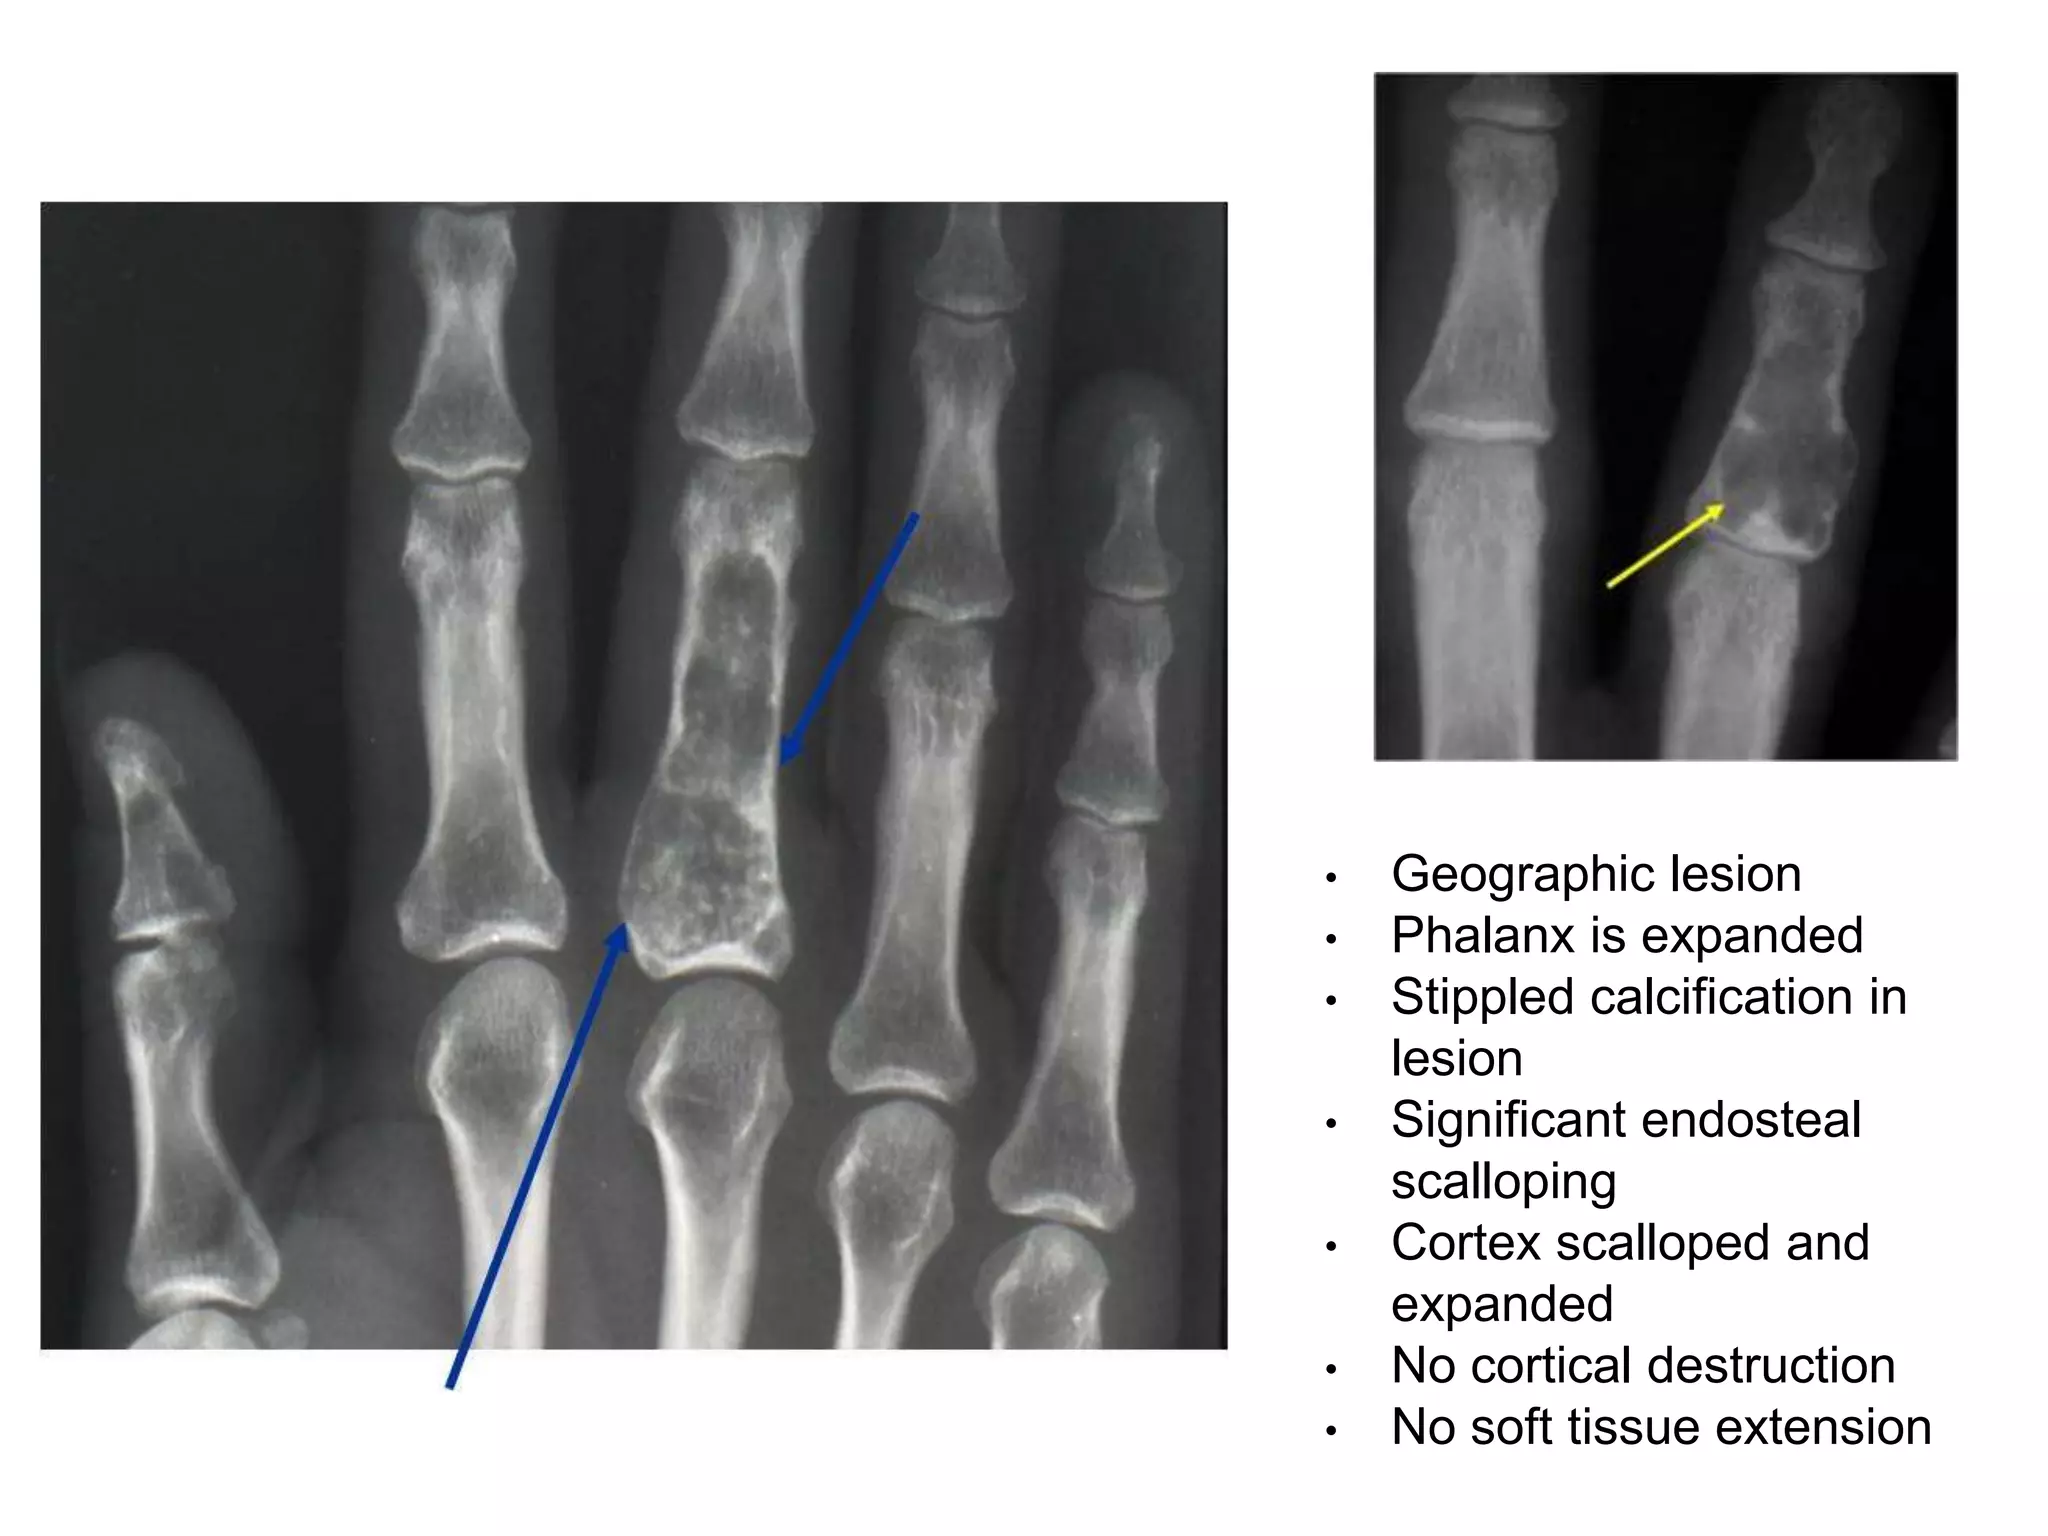

Enchondroma

•Benign condition

•Island of cartilage persist in metaphyses of bone

formed by endochondral ossification

•Pathology:

A lobulated mass of cartilage encapsulated

by fibrous tissue.

Intracellular matrix may undergo mucoid

degeneration

Frequently fibrous septae dividing lobules are

calcified

•Young adults (20-30 years old)

•In any bones preformed in cartilage

•Small bones of hands and feet commonly

• Usually asymptomatic

• Incidental finding on x ray or after pathological fracture

• Long standing swelling from one or more phalanges or

metacarpals, without much pain.

• The swelling increases in size very slowly, may eventually

replace the bone

• X ray:

Expanding lytic lesion in one or more bones

Overlying cortices are thinned out

Tumour matrix: stippled calcification

Mature lesion: Flecks or wisps of calcification within the

luscent area (pathognomonic feature)

• Geographic lesion

• Phalanx is expanded

• Stippled calcification in

lesion

• Significant endosteal

scalloping

• Cortex scalloped and

expanded

• No cortical destruction

• No soft tissue extension